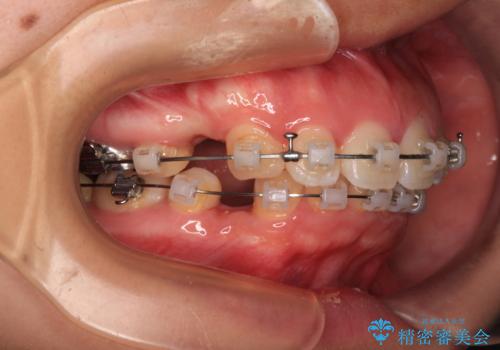

- 矯正装置

- クリアブラケット

- 治療期間

- 2年7ヶ月

上下正中位置を改善するため、左下はイレギュラーに第二小臼歯を抜歯しました。そのため治療期間の長期化が予想されましたが、2年半ほどで期待通りの歯列に仕上げることができました。